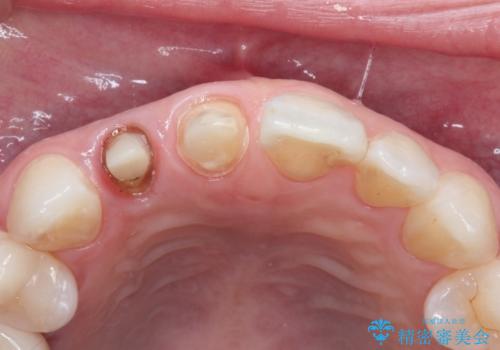

前歯が痛い。根管治療~オールセラミッククラウン

- 前歯が痛いことを主訴に来院されました。

根管治療を行った後、オールセラミッククラウン(エクセレント)にて治療を行いました。